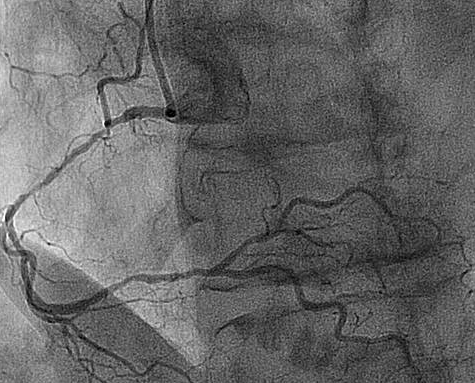

Multiple persisting opacifications of the coronary wall visible in more than one projection surrounding the complete lumen of the coronary artery at the site of the lesion.